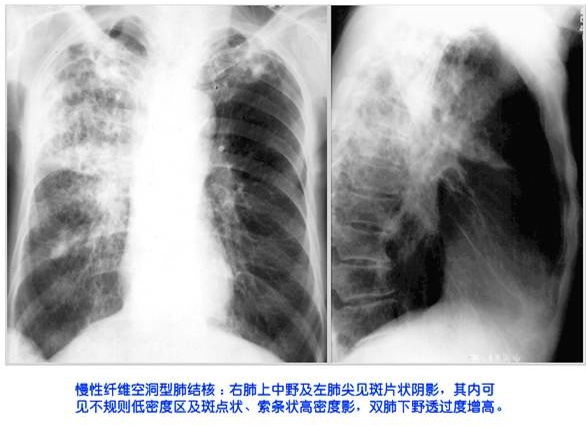

照片名称:慢性纤维空洞性肺结核